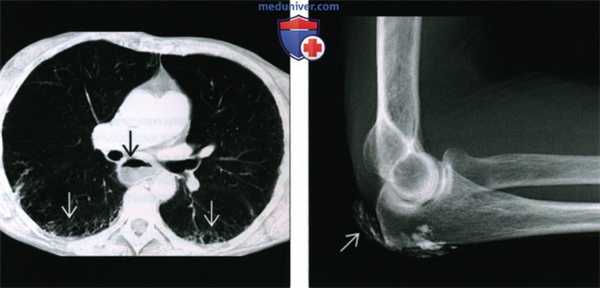

(Слева) КТ высокого разрешения, аксиальный срез: определяется расширение пищевода с уровнями воздух-жидкость, что говорит о нарушении моторики и интерстициальной болезни легких с поражением оснований. Поражение легких может обусловить тяжелое течение ПСС, и пациенты должны постоянно обследоваться на наличие поражения.

(Справа) Рентгенография в боковой проекции, этот же пациент: в подкожно-жировой клетчатке определяется плотный листовидный кальцификат. Хотя такая картина может наблюдаться при воспалительном миозите, она также наблюдается при ПСС, диагностированном у этого пациента.